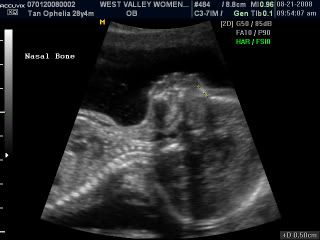

On Thurday... We went for a detailed scan. Mummy beanie told the sonographer that during week 12, when we were there, she told us that baby beanie is a boy and so... she check it once again. And she said, "Well... its still there, he is still a boy!" Haha... and we laughed. The scan went on really well. Baby beanie's very healthy and he is growing really well! Here's mummy beanie at the sonographer's diagnostic room and some pictures of baby beanie at 19 weeks! Enjoy!

Here's little beanie... Isn't he cute and round?

We think he has daddy's nose! Cause its all sharp and pointy... Mummy's really flat! Hehe...